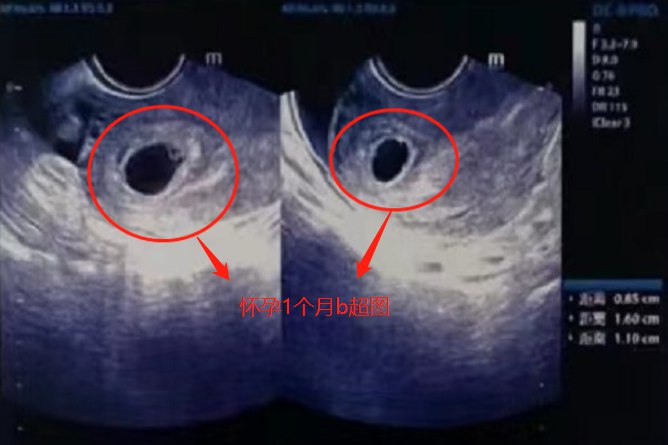

怀孕1个月即孕4周,属于早期妊娠,此时B超通常无法清楚地观察到宫腔内妊娠囊,一般要到孕6~7周时才可见。

怀孕1个月B超多不可见明显地表现,孕6~7周时可在宫腔内见圆形或椭圆形妊娠囊、胚芽以及原始心管搏动。